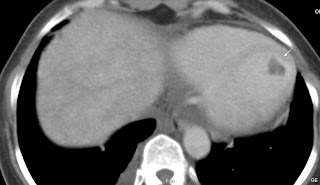

LV thrombus

Post a Comment for "Left Ventricle Thrombus-CT"